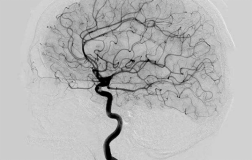

『护理科普』秋冬季脑血管疾病患者如何做好预防

随着气温持续下降,脑血管疾病进入高发期。据临床数据显示,当环境温度低于10℃时,脑血管疾病发病率会显著上升,尤其是中老年人群需重点警惕,科学预防与及时识别症状成为关键。一为何秋冬季节脑血管疾病高发?1.血管收缩风险:低温刺激会使全身血管急剧收缩,导致血压波动升高,增加血管...